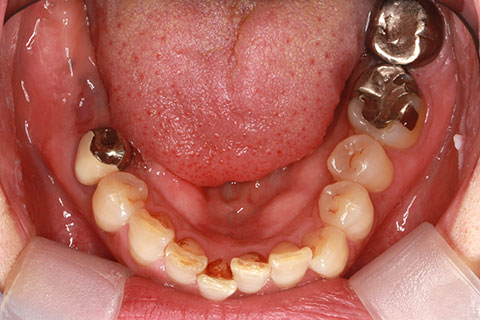

• 症例2

治療前

インプラント埋入時

治療後

年齢・性別

57歳男性

治療期間

3ヶ月

抜歯

なし

治療費

154万円

備考

左上5.6.7 及び左下6.7欠損

治療内容

左上5.6.7と左下6.7欠損部にインプラント埋入

施術の副作用(リスク)

オペによる知覚障害。インプラントによる歯肉炎。インプラント脱落。